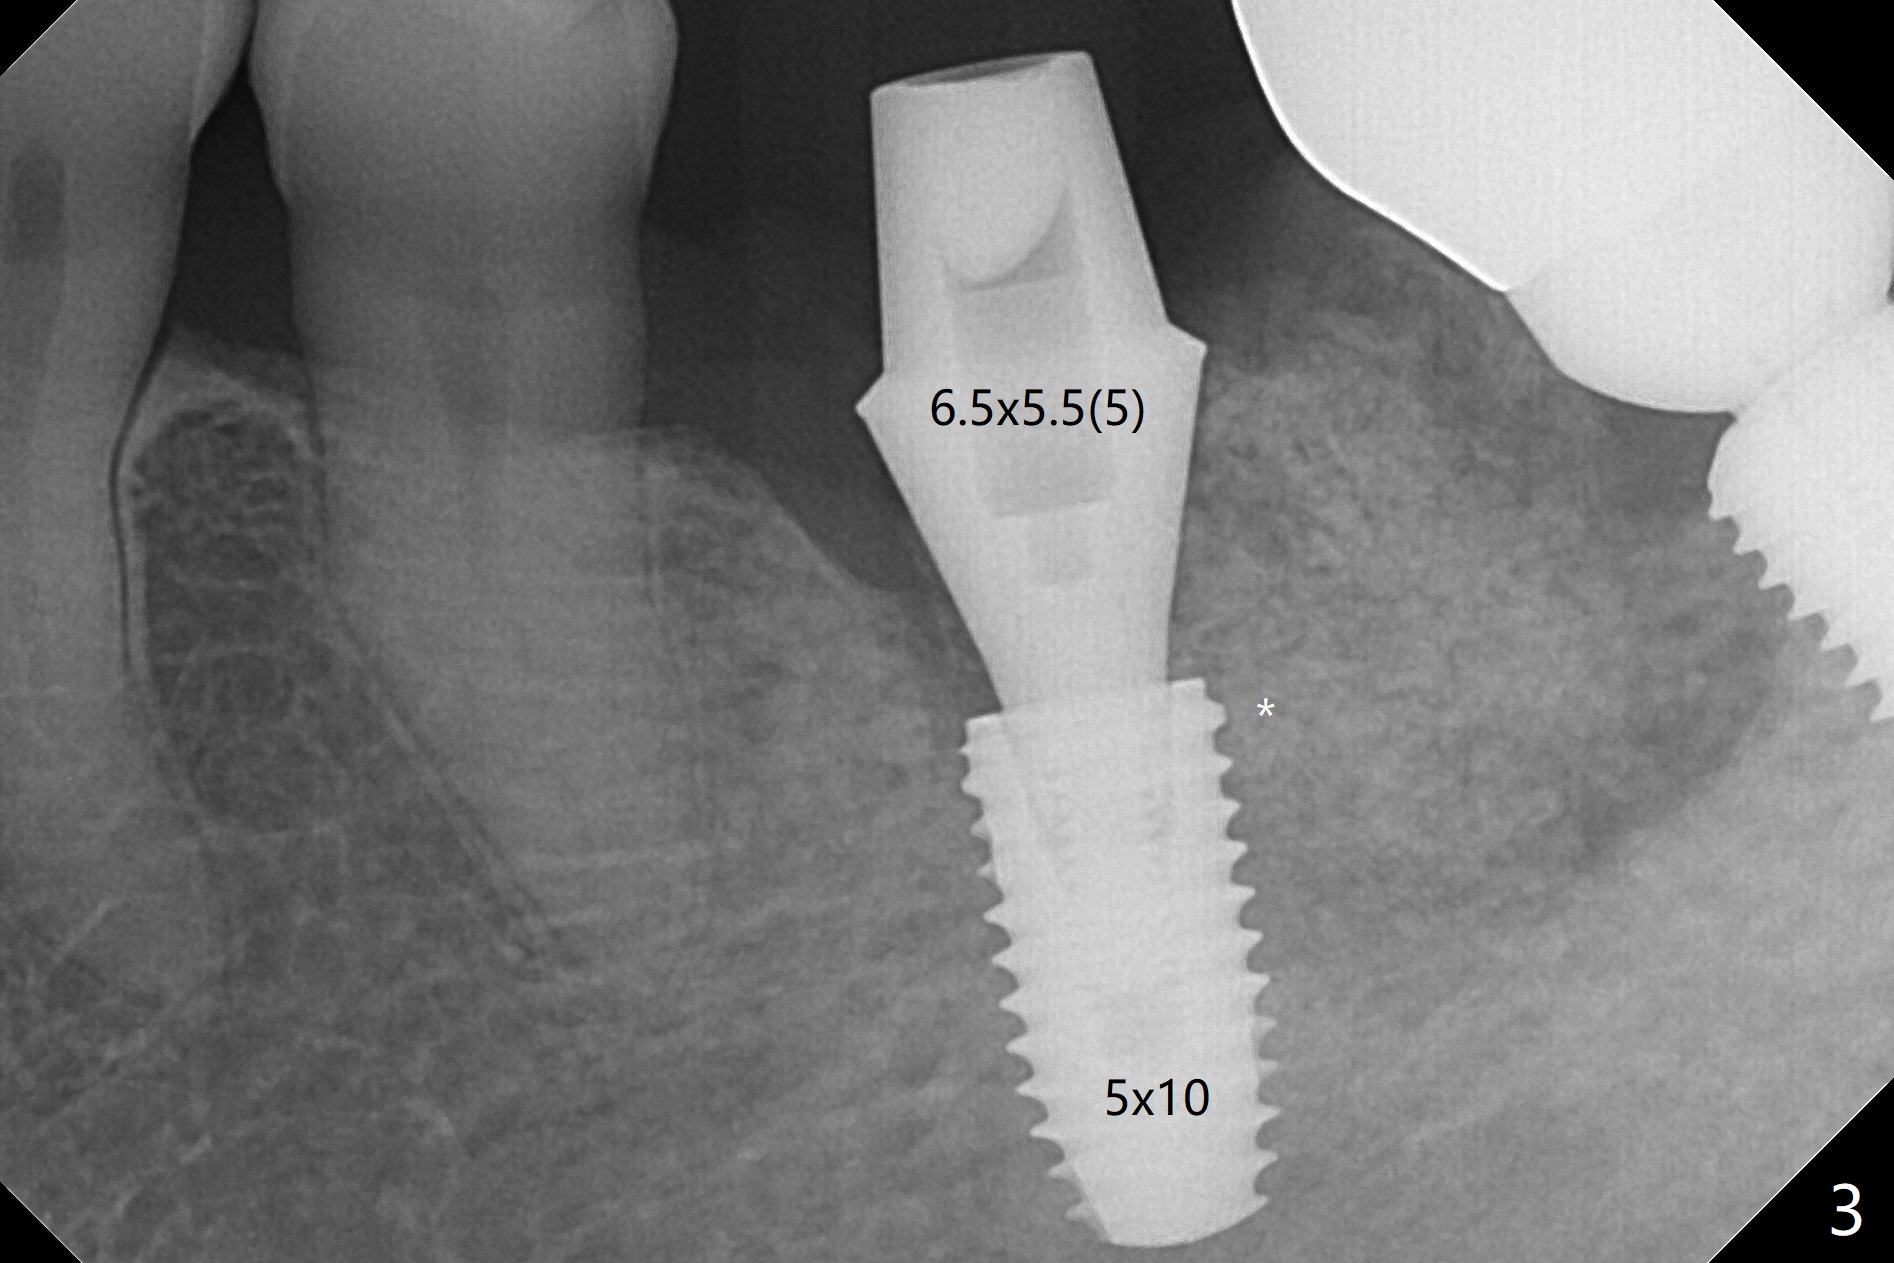

Probably due to severe infection at #19, pain control is difficult. Osteotomy has to be stopped 1.5 mm short of the design. PA taken with a 4.5x10 mm dummy implant does not show the Inferior Alveolar Canal (Fig.1), whereas CT does (Fig.2). With 6 mm clearance, block anesthesia is administered. A 5x10 mm definitive implant is placed with ease (Fig.3). The buccal bony defect is repaired by allograft (Fig.3,4 *), while the soft one by 3 pieces of PRF membrane (Fig.5). The latter is fixed in place by applying setting acrylic as an immediate provisional (Fig.6 P) over the wound, around the abutment (A) and locking into the undercut of the neighboring tooth/implant crown. The patient feels great postop. The gingiva is healthy around the provisional 8 days postop (Fig.7). The patient remains asymptomatic with the healthier gingiva surrounding the simplified provisional 22 days postop, as compared to 8 days postop (Fig.8). The socket heals when the simplified provisional is removed 1.5 months postop (Fig.9-12). The bone graft (Fig.11 ^) seems to have become a part of the regenerated gingiva. The abutment has been dislodged for 2 week (Fig.14 (3 months postop). The bone graft, albeit decreased, is 2 mm subgingival (red dashed line). There is bone distal to the implant 11 months postop (Fig.15 *). There is no bone loss 2 years postop; the UF abutment is completely seated (Fig.16).